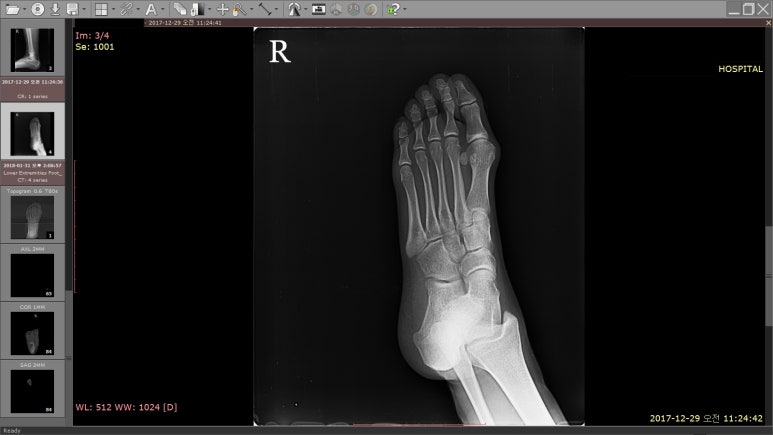

해당 환자분의 1달전 X-RAY 영상

1달 전, 발을 헛디뎌 넘어진 뒤

근처 병원에서 X-RAY를 찍었는데 골절은 아니라고 했답니다.